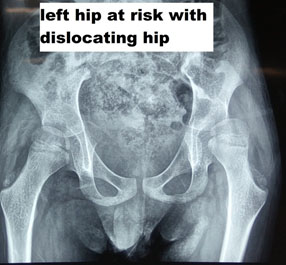

BONY PROCEDURE

A large number of times, CP kids tend to develop bony abnormality due to deforming muscle forces. The kids are born with normal bony architecture, but as they grow old, muscle spasticity causes deformity. The deformity at the hip could be a subluxation, flat foot, or in-toeing and out-toeing at the feet. The assessment of CP is incomplete without an objective evaluation of the muscular and bony deformity. If there are already bony changes that have developed, and if only muscular procedures are done, then they are bound to fail. Bony correction must also be done simultaneously.

Bony procedures in CP could consist of Osteotomies like Varus Derotation Osteotomy of the hip (VDRO) if the head and neck of the femur are vertical. We might need to add a Pelvic Osteotomy to give appropriate coverage for the head of the femur. There could be a need for derotation osteotomy of the leg (tibia) or the thigh bone (femur) to ensure that the child can walk appropriately or in Bedridden kid’s toileting activity is done easily.

What age should CP surgery be done?